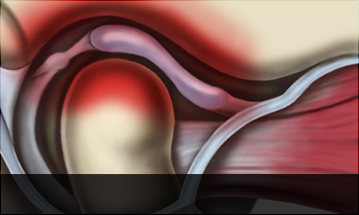

턱근육과 인대 손상 뿐만 아니라 턱관절에 관절염이 생긴 상태입니다. 외상 또는 기타 다른 이유로 턱관절 자체에 변형이 생기는 경우도 있습니다. 단순 관절염증의 경우 치료가 잘되는 경우가 많지만, 관절 자체의 변형이 심한 경우, 수술이 필요한 경우도 있습니다.

-

관절염

-

관절변형